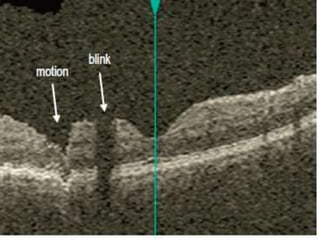

• Blink artifact : partial loss of data due to the

momentary blockage of OCT image acquisition

during the blink. recognized as black horizontal bars

across the OCT image.

• Motion artifact :occurs when there is movement of

the eye while scanning ->distortio.It is seen as a

sharp change in contour on the B-scan and as

misalignment of blood vessels.

• Blink artifact: partial loss of data due to the momentary blockage of OCT image acquisition during the blink. recognized as black horizontal bars across the OCT image. • Motion artifact :occurs when there is movement of the eye while scanning ->distortio.It is seen as a sharp change in contour on the B-scan and as misalignment of blood vessels.